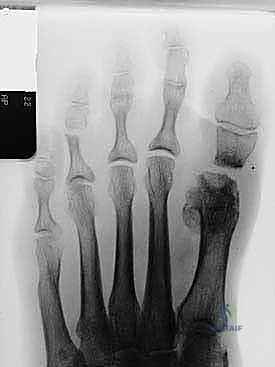

- التصوير بالأشعة السينية (X-rays): صور في وضعية الوقوف (تحمل الوزن) من زوايا متعددة لقياس زوايا التشوه بدقة وحساب مقدار الطول المفقود.

3. التشتيت وتحديد حجم الفجوة (Distraction)

باستخدام جهاز تشتيت متخصص (Distractor) أو ملقط جراحي، يتم سحب إصبع القدم برفق لإعادته إلى طوله الطبيعي ومحاذاته الصحيحة. يتم قياس الفجوة الناتجة بين العظم المشطي والسلامية بدقة بالمليمترات. هذا القياس يحدد حجم الطعم العظمي المطلوب.